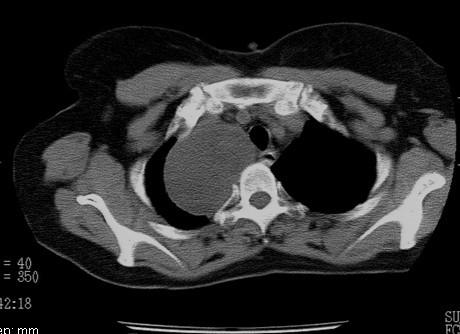

以下是引用随光逐影在2010-3-1 8:36:00的发言:[br]右上纵隔囊性占位性病变,考虑支气管囊肿,不排除神经源性肿瘤。